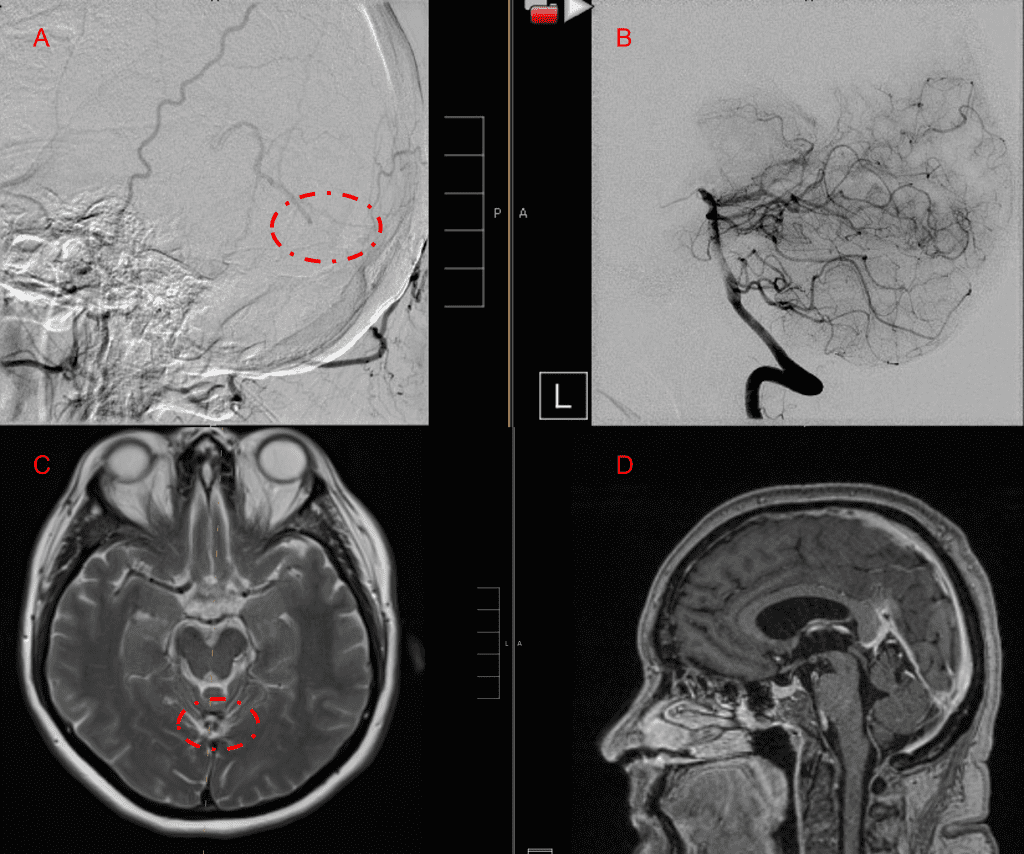

No severe neurologic deficits were observed initially. Her cerebral angiogram revealed a high flow Dural arterial venous fistulous malformation of the tentorium supplied by the bilateral external carotid and left vertebral arteries into a large venous varix within the fourth ventricle at the site of the hemorrhage. Deep venous drainage is observed into the Galenic and Straight Sinus of the posterior fossa (Figure 2).

Figure 2. [A] Ruptured Varix/Aneurysm of the Deep Venous Posterior Fossa drainage and AV shunting (arrows) [B] Posterior Meningeal Artery Fistula [C] Right Middle Meningeal Artery Fistula [D] Post embolization Left Vertebral Angiogram demonstrates resolution of the high flow and pressure A-V Shunting following successful embolization with liquid embolic (NBCA).